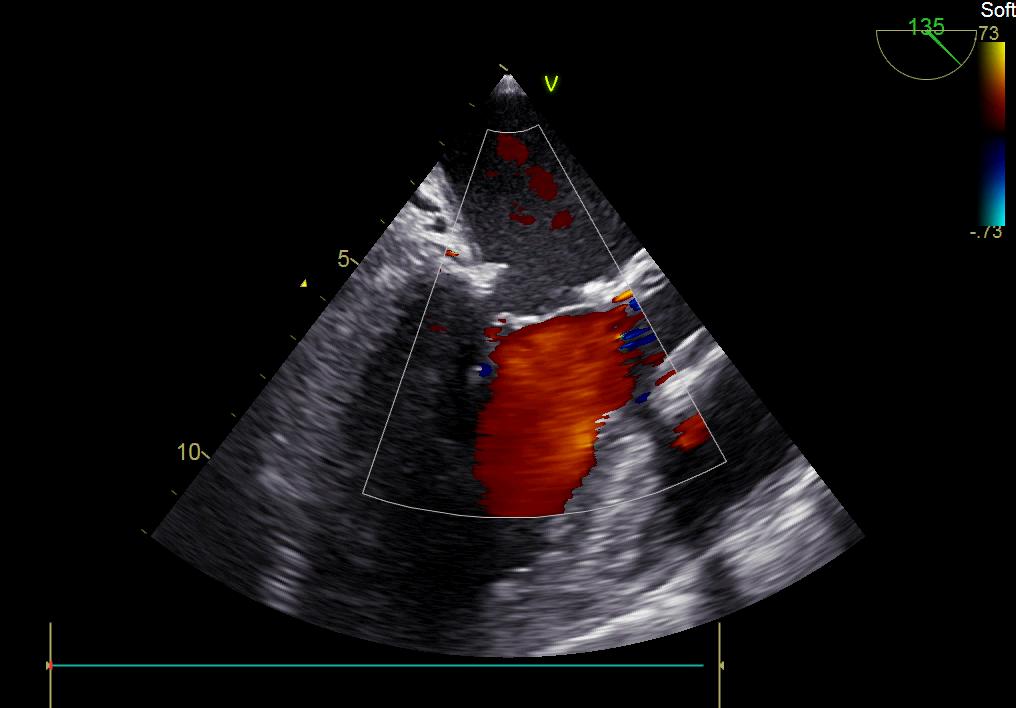

患者何某,42歲男性,因心功能不全入住我院心胸外科,心臟彩超提示二尖瓣后葉脫垂伴有重度返流及心臟擴(kuò)大,在迅速糾正心衰后,手術(shù)便提上日程,心胸外科廖金文主任多次組織全科及兄弟科室討論,在二尖瓣置換及成形術(shù)上,最終決定采取二尖瓣成形術(shù)。為保證手術(shù)安全,討論圍手術(shù)期各個細(xì)節(jié),所謂細(xì)節(jié)決定成敗,因為術(shù)前的細(xì)致全面,加上術(shù)中的一絲不茍及術(shù)后的精細(xì)化管理,患者術(shù)后恢復(fù)順利,健康出院,復(fù)查心臟彩超未見二尖瓣返流。

術(shù)后彩超